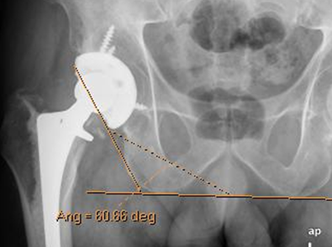

El componente acetabular es colocado con una inclinación lateral de 40º, en relación con la vertical. Se mide en una Rx AP de pelvis, trazando un ángulo entre el borde inferior de la copa acetabular y la línea que une el borde inferior de las tuberosidades isquiáticas. (32). (Fig 118).

Fig 118. Angulo de inclinación normal.

Rx AP. Medido entre la inclinación del componente acetabular y una línea que une las espinas isquiáticas.

Rx AP. Incremento del ángulo de inclinación acetabular (60º), existiendo alto riesgo de luxación de la prótesis.